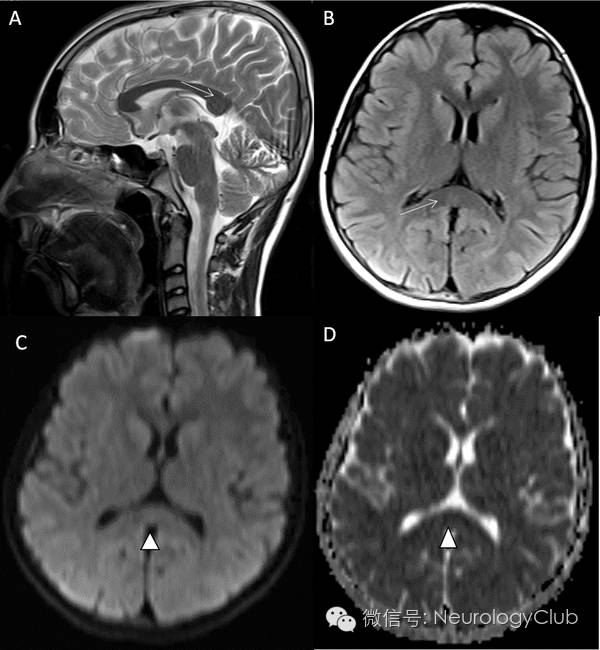

(图1:抗VGKC抗体相关的RESLES。起病7天后MRI上可见SCC病灶,22天后病灶消失。A与C:DWI;B与D:ADC